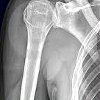

Рентгенография плечевой кости

Рентгенография костей. Рентгенологическое исследование, показанием которого является подозрение на перелом ствола, периостит, остеомиелит, доброкачественную или злокачественную опухоль плечевой кости. Стандартный тест проводится в двух планах (прямой и боковой вид). В некоторых случаях сначала делается снимок в одной проекции, а после обнаружения патологии назначается второе рентгеновское изображение для объяснения природы и местоположения поражений. Требуется специальное обучение. В детстве и во время беременности обычные рентгеновские снимки заменяются другими методами (КТ, МРТ). При наличии аварийных показаний нет никаких ограничений по тесту.

В травматологии рентгенография плечевой кости назначается при подозрении на перелом плечевого ствола, остеомиелит или периостит. В других областях медицины (онкология, хирургия, ортопедия) методика может быть использована для выявления пороков развития, злокачественных и доброкачественных опухолей и оценки участия костных структур плеча в гнойно-воспалительном процессе. Противопоказанием к планируемому исследованию считается возраст детей и срок беременности. При неотложной патологии, угрожающих жизни состояниях, невозможности использования других инструментальных методов диагностики (МРТ, КТ, УЗИ) противопоказаний нет.